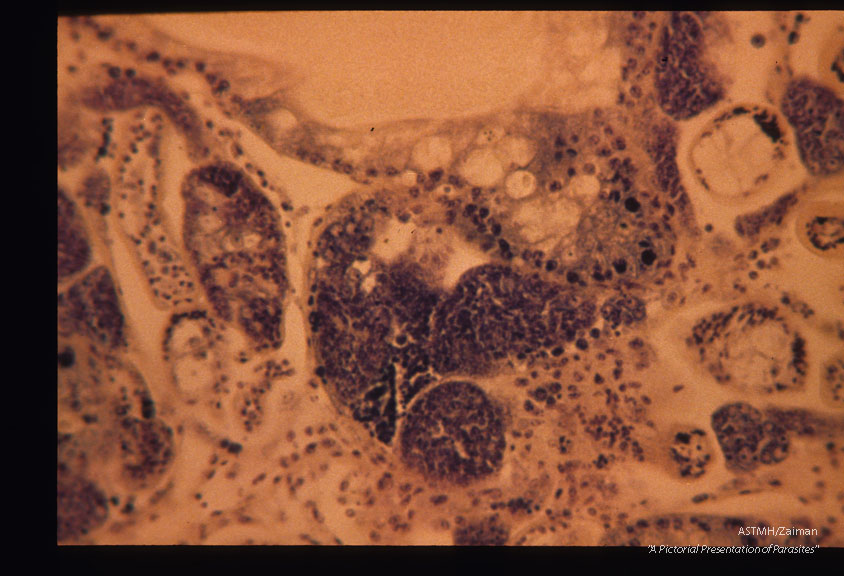

Sections through snail (Biomphalaria glabrata) liver containing sporocysts 54 days after infection.

Schistosoma mansoni

Description: Sections through snail (Biomphalaria glabrata) liver containing sporocysts 54 days after infection.